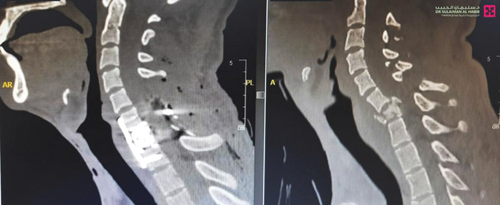

وقال الدكتور ناجي مسعود استشاري جراحة المخ والأعصاب، إن الشاب أسعف إلى طوارئ المستشفى في حالة معقدة، فاقداً للوعي بنسبة كبيرة، مع اضطرابات في ضربات القلب، وشلل تام وعدم شعور في الأطراف السفلية، بالإضافة إلى شلل بدرجة 3/5 في اليدين، كما أنه تعرض لصدمة شديدة نتيجة إصابة النخاع الشوكي، مما أدى إلى هبوط في الضغط، وفور وصوله إلى الطوارئ وضع على جهاز التنفس الصناعي للمحافظة على وظائفه الحيوية، وبعد استقرار حالته أجريت للمريض فحوصات طبية دقيقة أظهرت نتائجها، كسراً حاداً ومركباً في الفقرة العنقية السابعة، وضغطاً شديداً على النخاع الشوكي وتورماً متمدداً من الفقرة السابعة العنقية إلى الفقرة الخامسة من العمود الفقري، وهو الأمر الذي ترتب عليه معظم الأعراض الحادة التي جاء بها المصاب إلى المستشفى. وأضاف د. مسعود أن الفريق الطبي بعد دراسة الحالة انتهى إلى ضرورة التدخل الجراحي، إلا أنه مع تورم النخاع الشوكي، وتدهور العلامات الحيوية لم يكن من الممكن إجراء العملية في اليوم نفسه، فانتظرنا إلى أن تحسنت حالة النخاع الشوكي والعلامات الحيوية، ثم قمنا باجراء عملية دقيقة تم فيها إزالة الفقرة السابعة بالكامل، وزراعة فقرة صناعية من التيتانيوم وتثبيتها بالصفيحة والبراغي، وتحرير النخاع الشوكي من الضغط، وتكللت العملية التي استمرت لنحو «5» ساعات ولله الحمد بالنجاح، وبدأ المريض تدريجياً في تحريك أطرافه السفلية واستعادة الشعور فيها في اليوم التالي للعملية، وغادر المستشفى على «المشاية» بعد عدة أيام أمضاها قيد الرعاية الطبية الحثيثة، وعندما عاد للمراجعة جاء يمشي على قدميه مع بعض المساعدة «متكئاً على عصا»، لكن كافة المؤشرات الطبية تؤكد أنه مع العلاج الطبيعي سيستعيد قدرته على المشي بصورة طبيعية.

وأوضح د.مسعود أن العملية اتصفت بالتعقيد، وذلك بسبب جسامة الإصابات التي لحقت بالمريض وحساسية موقعها، فضلاً عن الحالة الصحية العامة الدقيقة التي وصل بها إلى المستشفى، مضيفاً أن كفاءة الفريق الطبي والتجهيزات المتقدمة التي يحظى بها المستشفى ساهما في نجاح العملية، وإنقاذ هذا الشاب من المضاعفات الوخيمة التي كانت من الممكن أن تصيبه بالشلل، أو تعرض حياته إلى الخطر لا سمح الله.